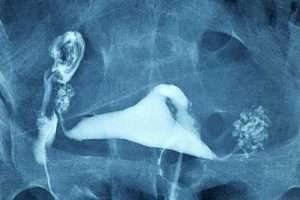

İki Taraflı Salpenjitis Istmica Nodosa (SIN) ve Hidrosalpinks

Bilateral Salpenjitis Istmica Nodosa (SIN)